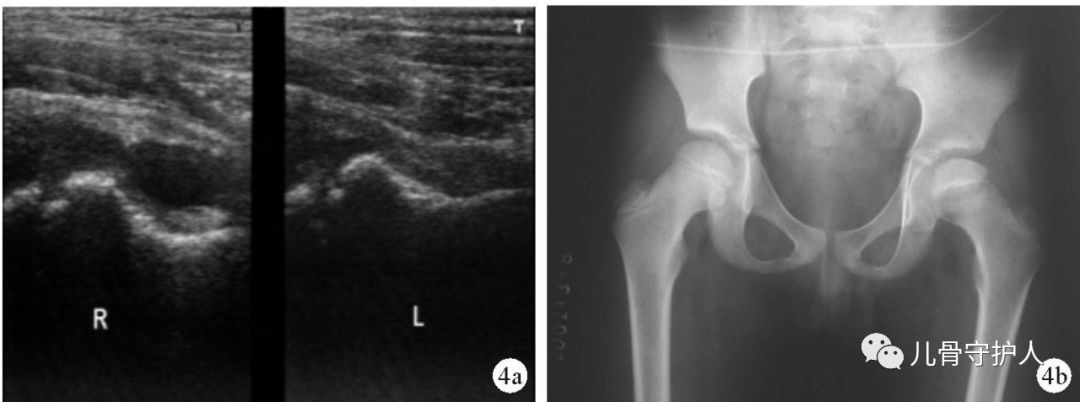

4.X:骨盆轻度倾斜,髋关节囊肿胀,关节间隙增宽,无骨质破坏。B超:患髋股骨颈颈前间隙增宽,双侧差值大于1mm。滑膜增厚,关节积液。